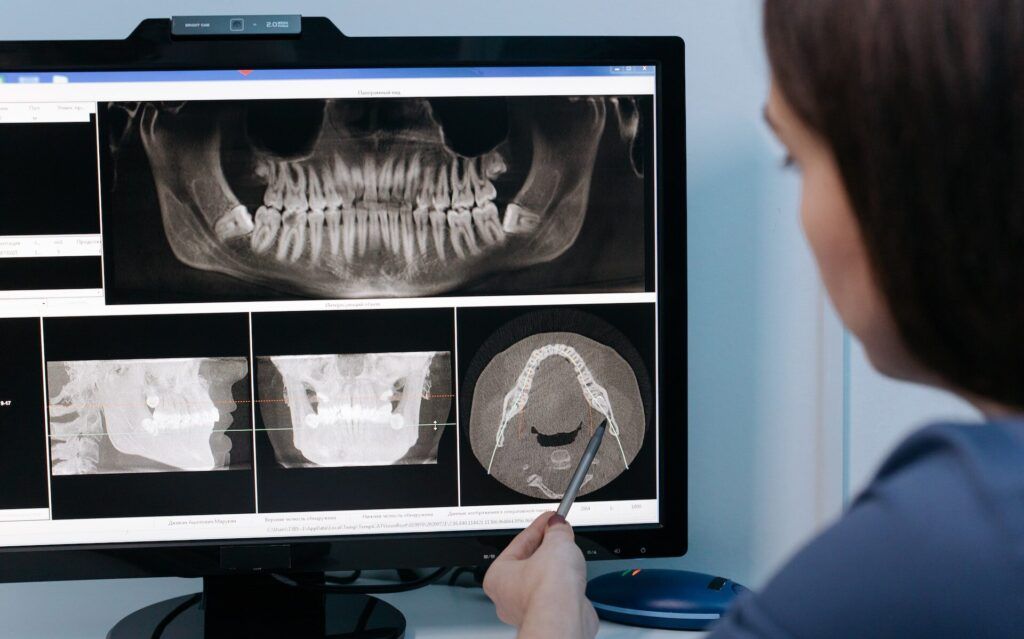

Диагностика

Врач проводит визуальный осмотр и делает прицельный рентгеновский снимок для оценки глубины поражения.

Мы всегда стараемся максимально сохранить здоровый зуб, удаляя только зараженные участки. Точная диагностика позволяет определить границы поражения кариесом и не заходить за её пределы. При ранней стадии работаем в технологии ICON — лечим без сверления.